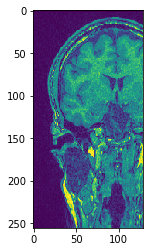

复制切片#

为了可视化特定的切片,而不让图像离开GPU内存,请使用copy_slice方法。

# Copy Slice

image_slice = cle.create([256, 256]);

slice_z_position = 40.0;

cle.copy_slice(input_image, image_slice, slice_z_position)

# show result

cle.imshow(image_slice)

../_images/c60c6141e977151383e4e4988e95e2b2a8a313b44d0ead1d5e0cbcf484394c62.png